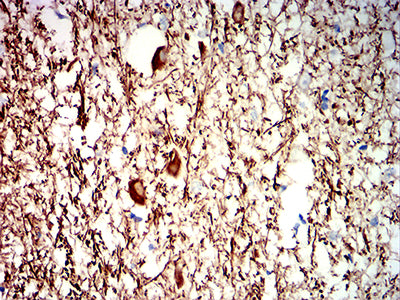

Immunohistochemical analysis of paraffin-embedded human cerebrum tissues using NEFH mouse mAb with DAB staining.

-

Immunohistochemical analysis of paraffin-embedded human cerebellum tissues using NEFH mouse mAb with DAB staining.